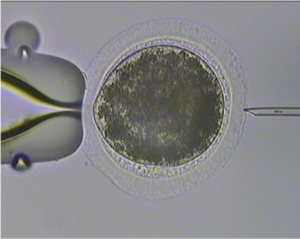

First Equine Embryo Time-Lapse Images Revealed

Do you think horses are quick to get moving right after birth? Check out what they’re doing right after fertilization.